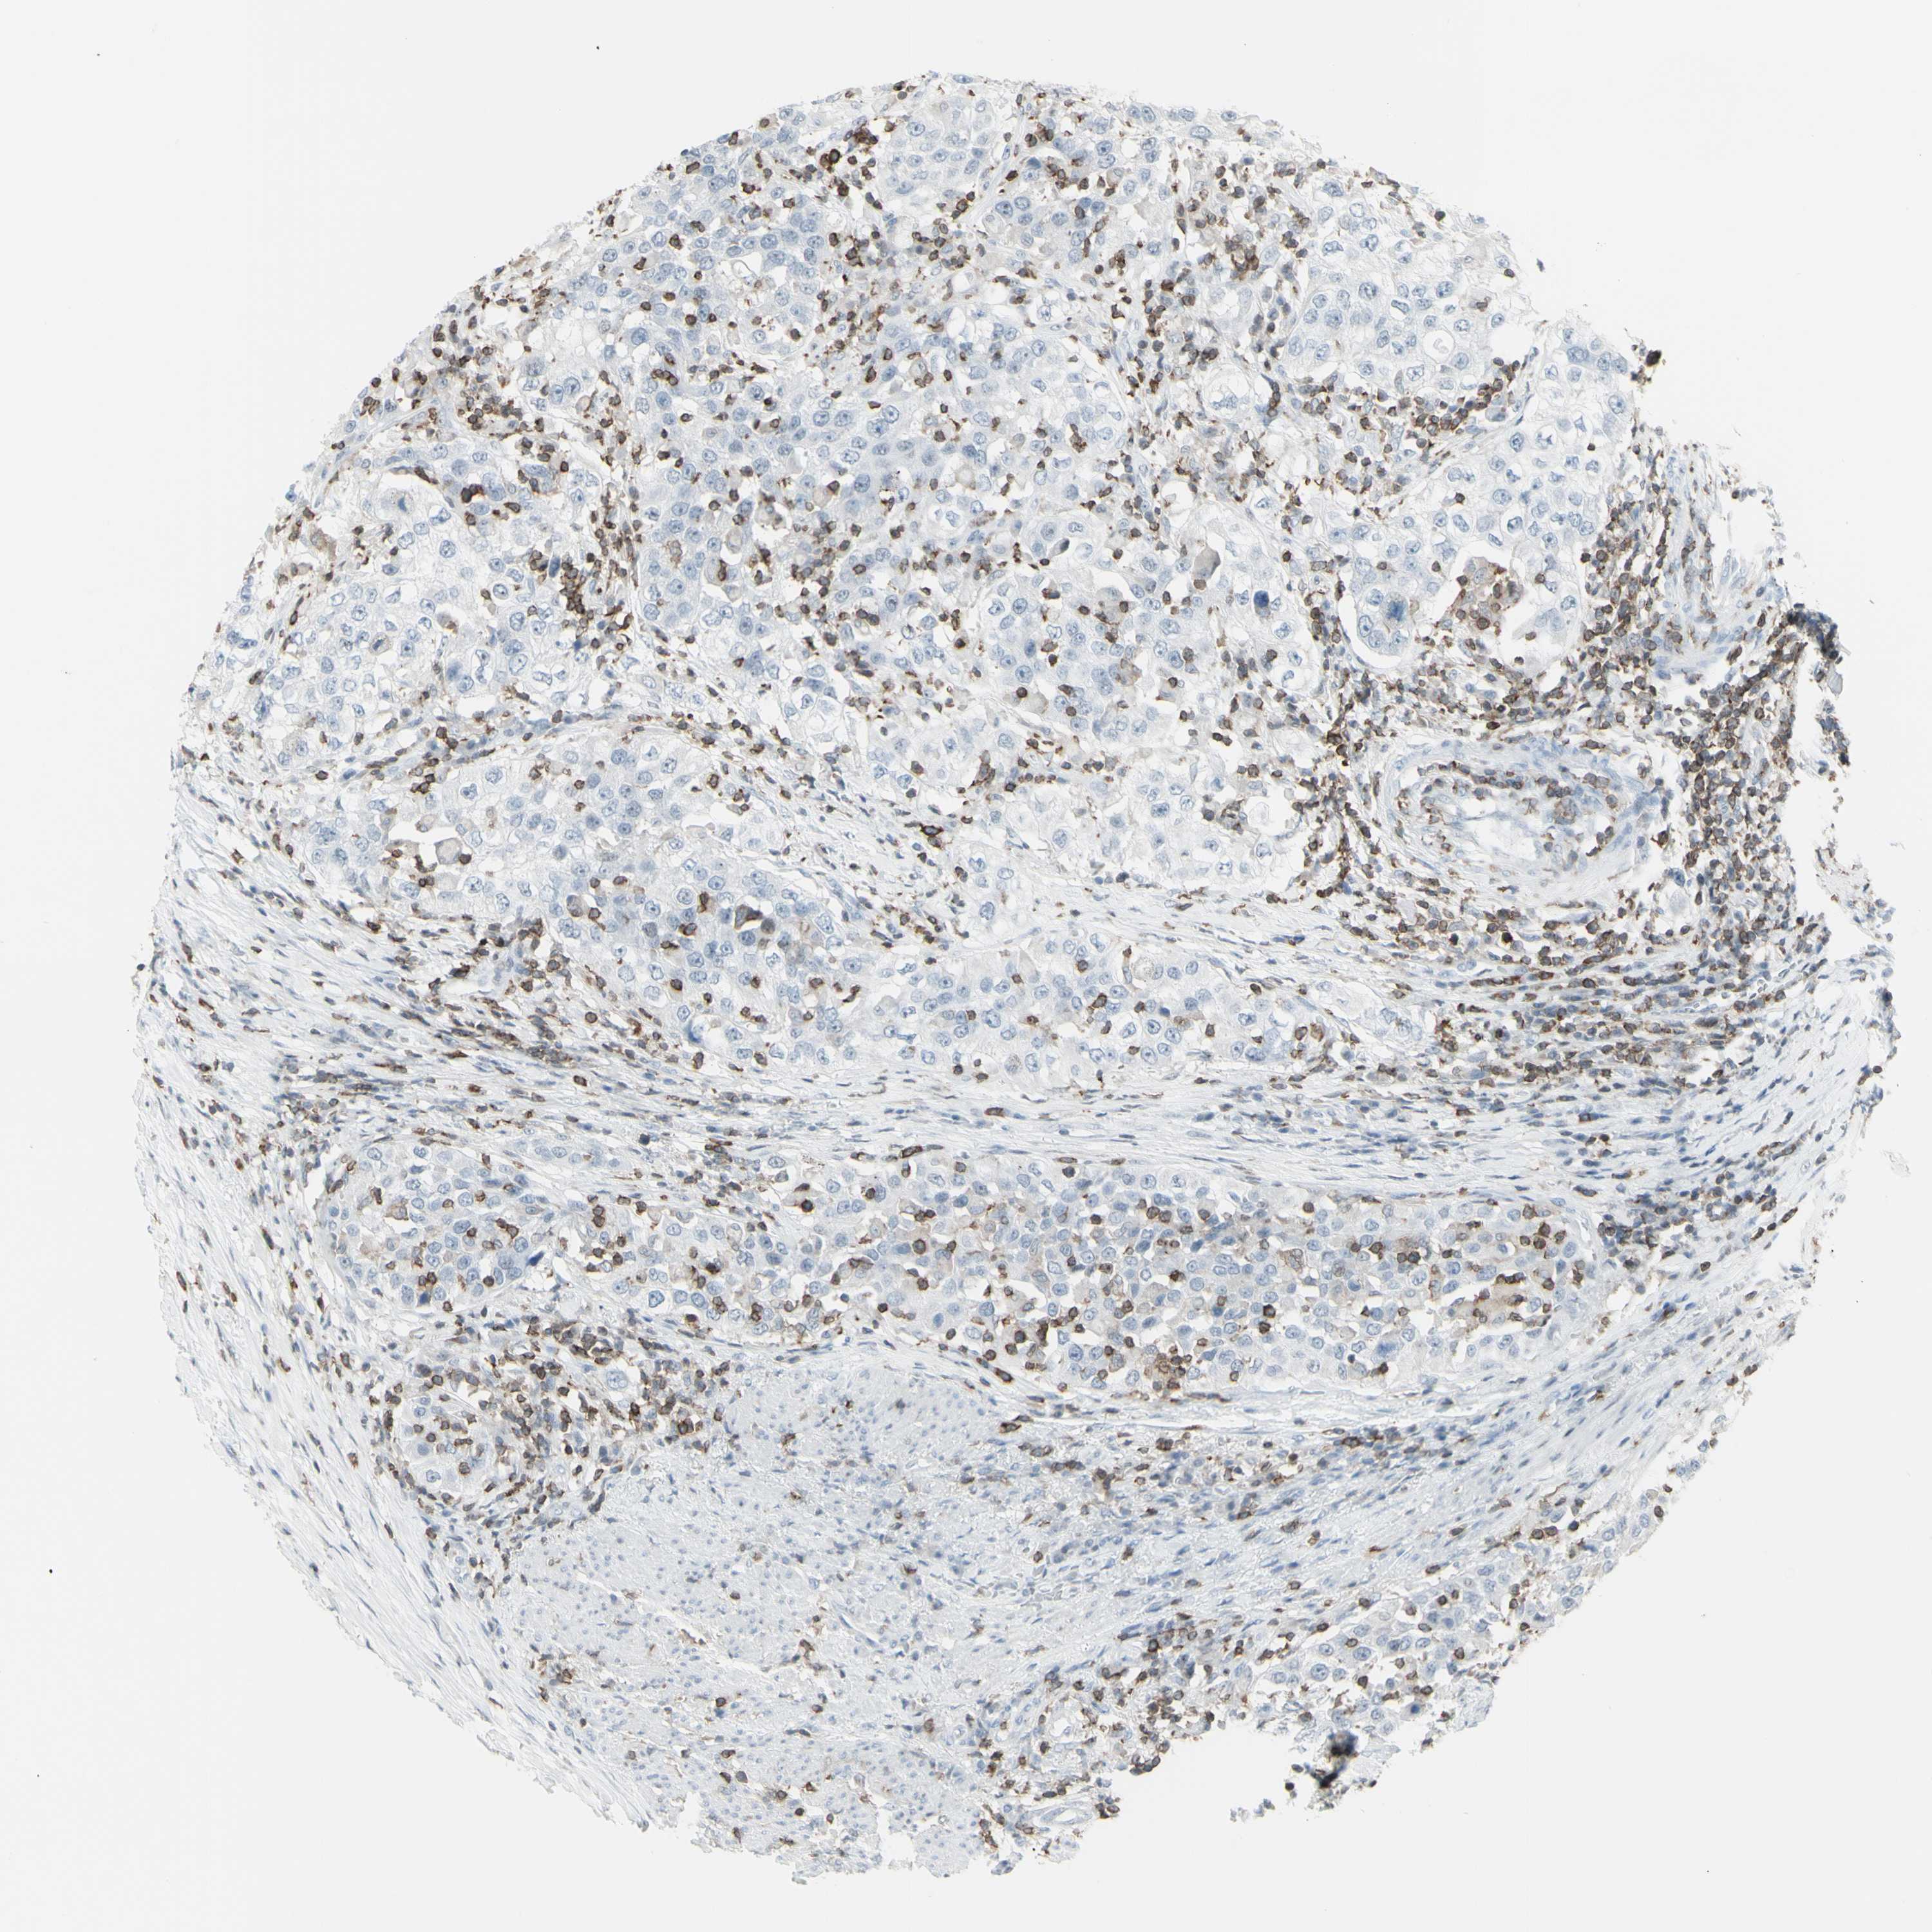

UROTHELIAL CANCER - Protein expressioni

A mouse-over function shows sample information and annotation data. Click on an image to view it in a full screen mode. Samples can be filtered based on level of antibody staining by selecting one or several of the following categories: high, medium, low and not detected. The assay and annotation is described here.

Antibody stainingi

Antibody staining in the annotated cell types in the current human tissue is reported as not detected, low, medium, or high, based on conventional immunohistochemistry profiling in selected tissues. This score is based on the combination of the staining intensity and fraction of stained cells.

Each image is clickable and will lead to virtual microscopy that enables deeper exploration of all samples and also displays staining intensity scores, fraction scores and subcellular localization as well as patient and tissue information for each sample.

Antibody HPA010964

Staining

High

Medium

Low

Not detected

Intensity

Strong

Moderate

Weak

Negative

Quantity

>75%

75%-25%

<25%

None

Location

Nuclear

Cytoplasmic/membranous

Cytoplasmic/membranous,nuclear

Urothelial carcinoma, Low grade

Urothelial carcinoma, High grade